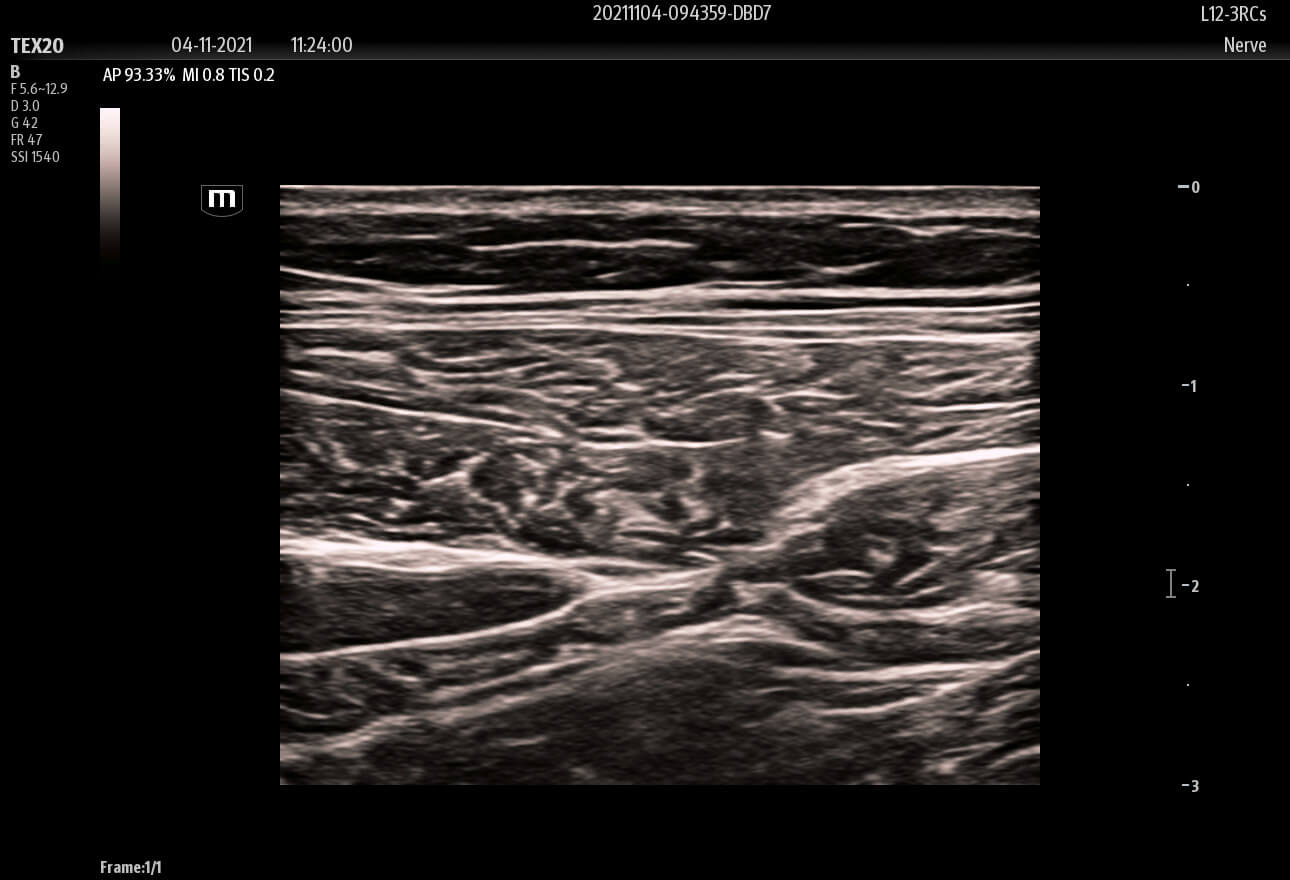

Enhancing Clinical Confidence

Advanced Technologies